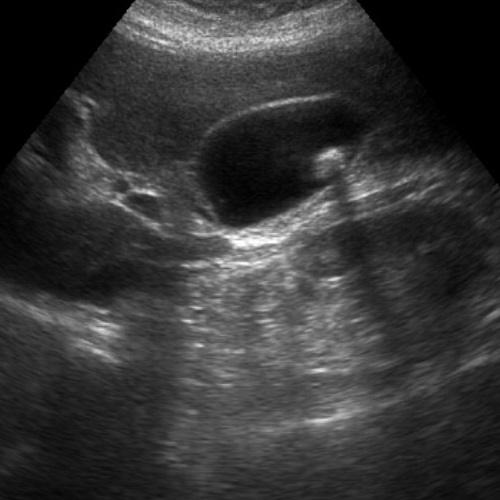

La diagnosi ecografica della diastasi dei retti addominali è uno dei metodi più accurati e non invasivi per valutare l'entità della separazione tra i muscoli retti addominali e monitorarne l'evoluzione. Durante l'esame, l'ecografo permette di visualizzare i muscoli addominali e la linea alba, misurando la distanza tra i muscoli retti nella posizione di riposo e durante contrazioni leggere, come ad esempio un sollevamento della testa o delle spalle.

1. Ampiezza della separazione: si misura lo spazio tra i muscoli retti, generalmente a livello della regione sopra e sotto l'ombelico. Una distanza superiore a 2-2,5 cm è spesso indicativa di diastasi.

2. Integrità della linea alba: si valuta il grado di assottigliamento o cedimento del tessuto connettivo, che influisce sulla capacità di supporto dell'addome.

3. Coinvolgimento delle strutture circostanti: l’ecografia può rilevare eventuali ernie o alterazioni della struttura muscolare e connettiva che potrebbero richiedere un trattamento specifico.